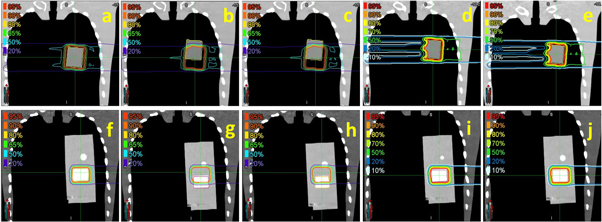

The CTV coverage (V95%) and dose distributions in both scenarios are illustrated in figures 4 and 5. The CTV coverage (V95%) differences between InRoom-BM and DVM-BM and between the InRoom-TM and the DVM-TM, were minor in both scenarios (0.46% and −0.28% for scenario 1, −1.95% and −0.38% for scenario 2, respectively; figure 4). The dose distributions of the DVM-BMs (figures 5(c) and (h)) were similar to those of the InRoom-BMs (figures 5(b) and (g)), as were the DVM-TMs (figures 5(e) and (j)) and the InRoom-TMs (figures 5(d) and (i)). With different isocenters, the dose coverage of the DVM CT changed consistently with those of the in-room CT, indicating that estimating daily dose distribution from two radiographs was feasible.

Standard image High-resolution imageFigure 5. Isodose lines for each scenario ((a)–(e) for cuboid, (f)–(j) for cylindrical insertions) in phantom simulations. (a) and (f) are isodose lines of PlanCT, (b) and (g) are InRoom-BM, (c) and (h) are DVM-BM, (d) and (i) are InRoom-TM, and (e) and (j) are DVM-TM.

Download figure:

Standard image High-resolution image3.2. Clinical data results